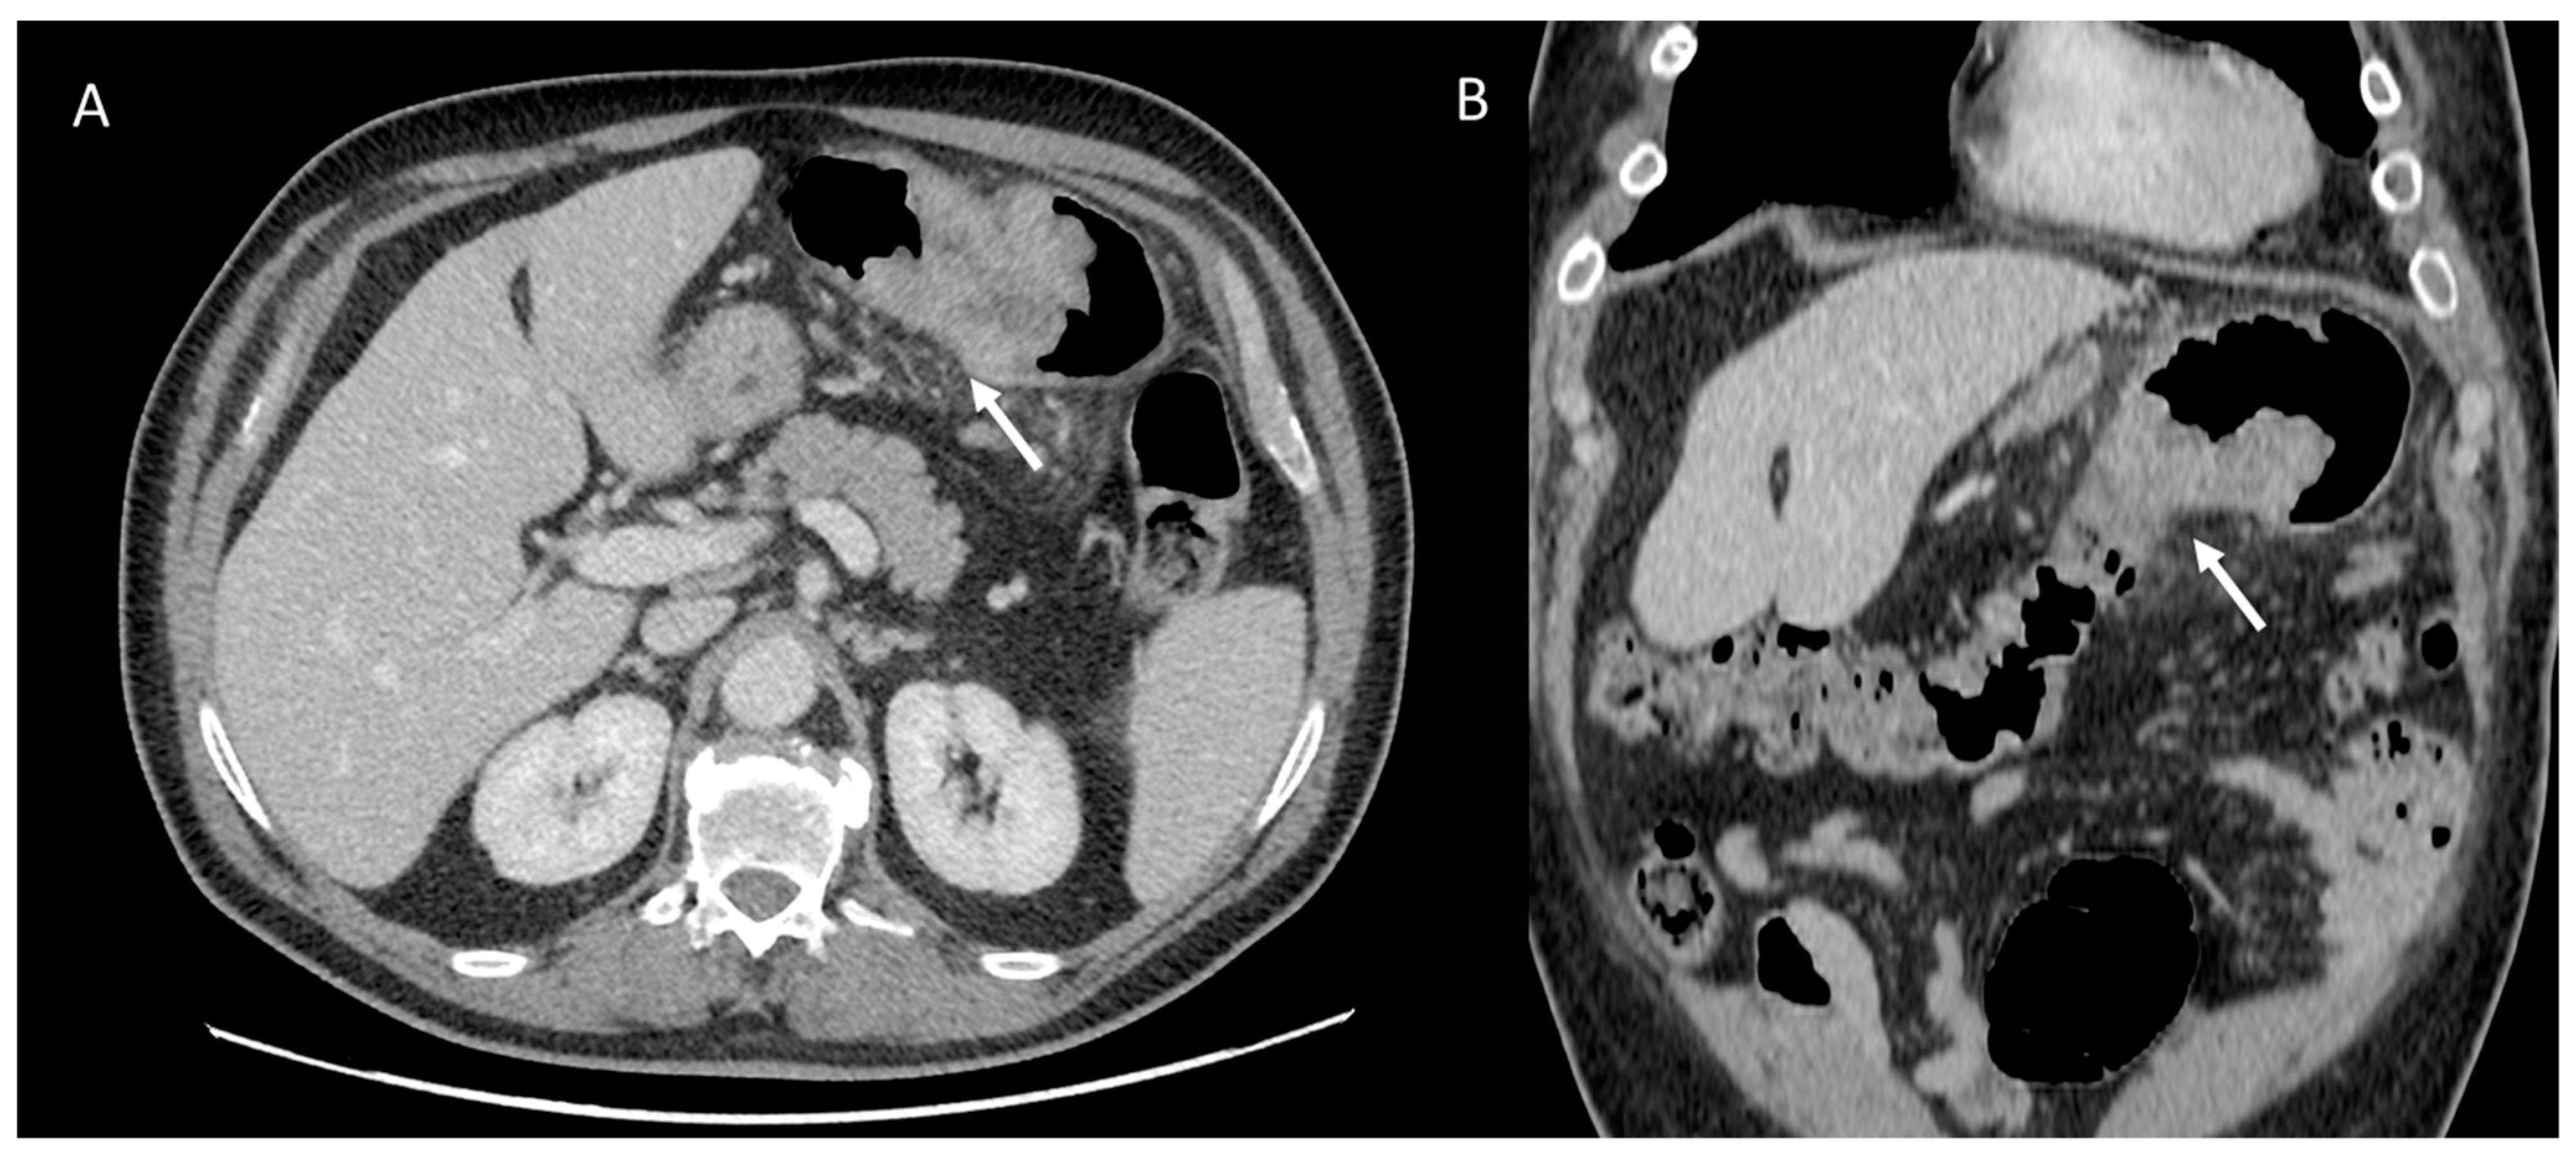

IPF is a chronic, irreversible, disabling disease with a fatal outcome characterized by a progressive decline in lung function. It is associated with a radiological pattern of usual interstitial pneumonia (UIP). In the literature, women have shown less fibrotic alterations than their male counterparts at HRTC (Figure 4).

Figure 4.

(A) Diffuse ground glass opacities with reticular thickening of the subpleural interstitium (white arrow), together with traction bronchiectasis in a case of pulmonary fibrosis with UIP pattern and smoking-related interstitial lung disease (ILD) in a female smoker. (B) A typical UIP pattern in a male smoker with idiopathic pulmonary fibrosis, together with diffuse ground glass opacities (white arrow) during an acute exacerbation.

A French multicenter prospective study [104] explored gender differences in an IPF cohort over a 5-year follow-up period. The cohort included 51 (22%) females and 185 (78%) males with a mean age at diagnosis of 70.1 ± 9.20 and 67.4 ± 10.9 years, respectively. At presentation, honeycombing and emphysema at HRCT were less common in females: (n = 40 (78.4%) vs. n = 167 (90.3%), p = 0.041) and (n = 6 (11.8%) vs. n = 48 (25.9%), p = 0.029), respectively. Fewer women than men also underwent transplantation during follow-up (n = 1 (1.96%) vs. n = 20 (10.8%), p = 0.039).